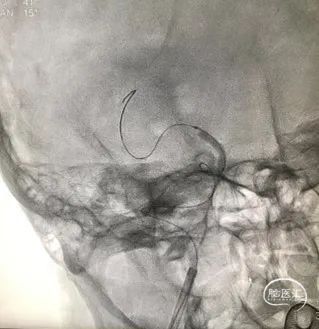

导引导管到位,导丝通过病变。

球囊通过病变

球囊扩张过程